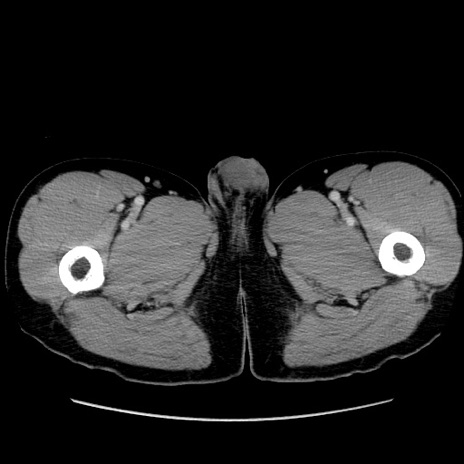

症例36(横断像)

【症例】20歳代 男性

【主訴】心窩部痛

【現病歴】今朝より上腹部痛あり。一旦軽快していたが再度出現したため救急要請。昨日夕に白身の魚を含む刺身を食べた。

【身体所見】BP 136/89mmHg、HR 74/min、BT 37.0℃、腹部:膨満、軟、心窩部に圧痛あり。反跳痛なし、筋性防御なし、腸雑音やや亢進あり。

【データ】WBC 17700、CRP 0.48